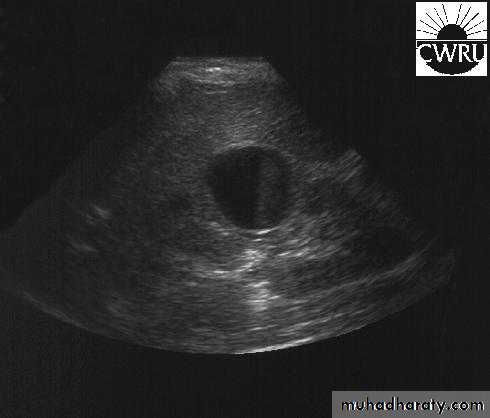

U/S: cystic cortical lesion with internal echoes.

U/S cystic lesion with internal echoes (renal abscess)